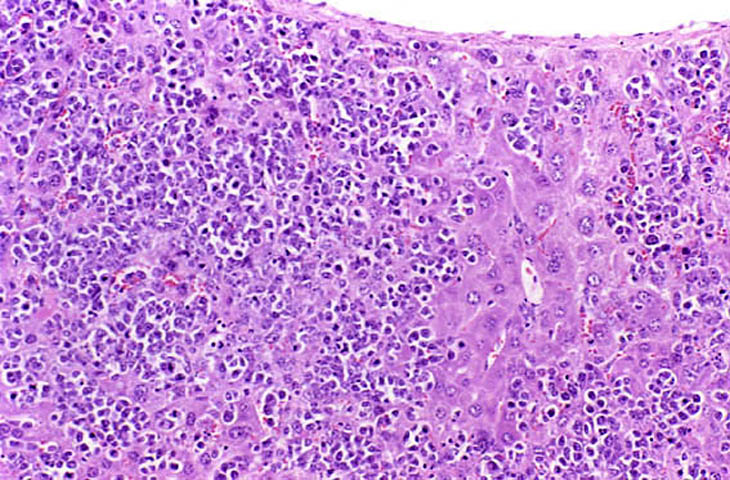

The liver is a relatively frequent site of infiltration by malignant lymphocytes, especially in strains with a high prevalence of lymphoma.

Infiltration of malignant lymphocytes in a liver from an adult mouse.

Severe infiltration of the liver by malignant lymphocytes. Hepatocytes visible in the lower right corner.